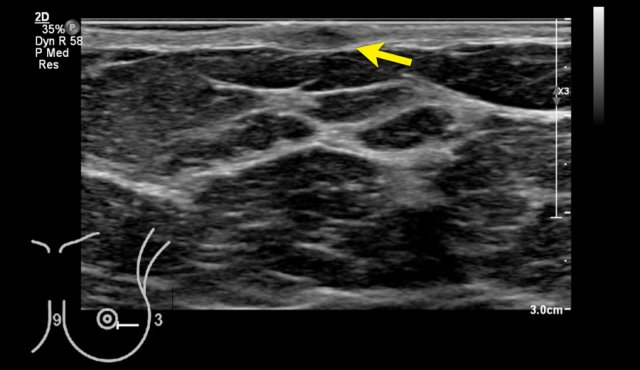

When you look at the contour of the glandular tissue (arrow), you can imagine, that this can feel bumpy on palpation and sometimes give the impression of a mass, when it is very pronounced.

The way that the breasts present on an ultrasound image may differ between machines of different manufacturers.